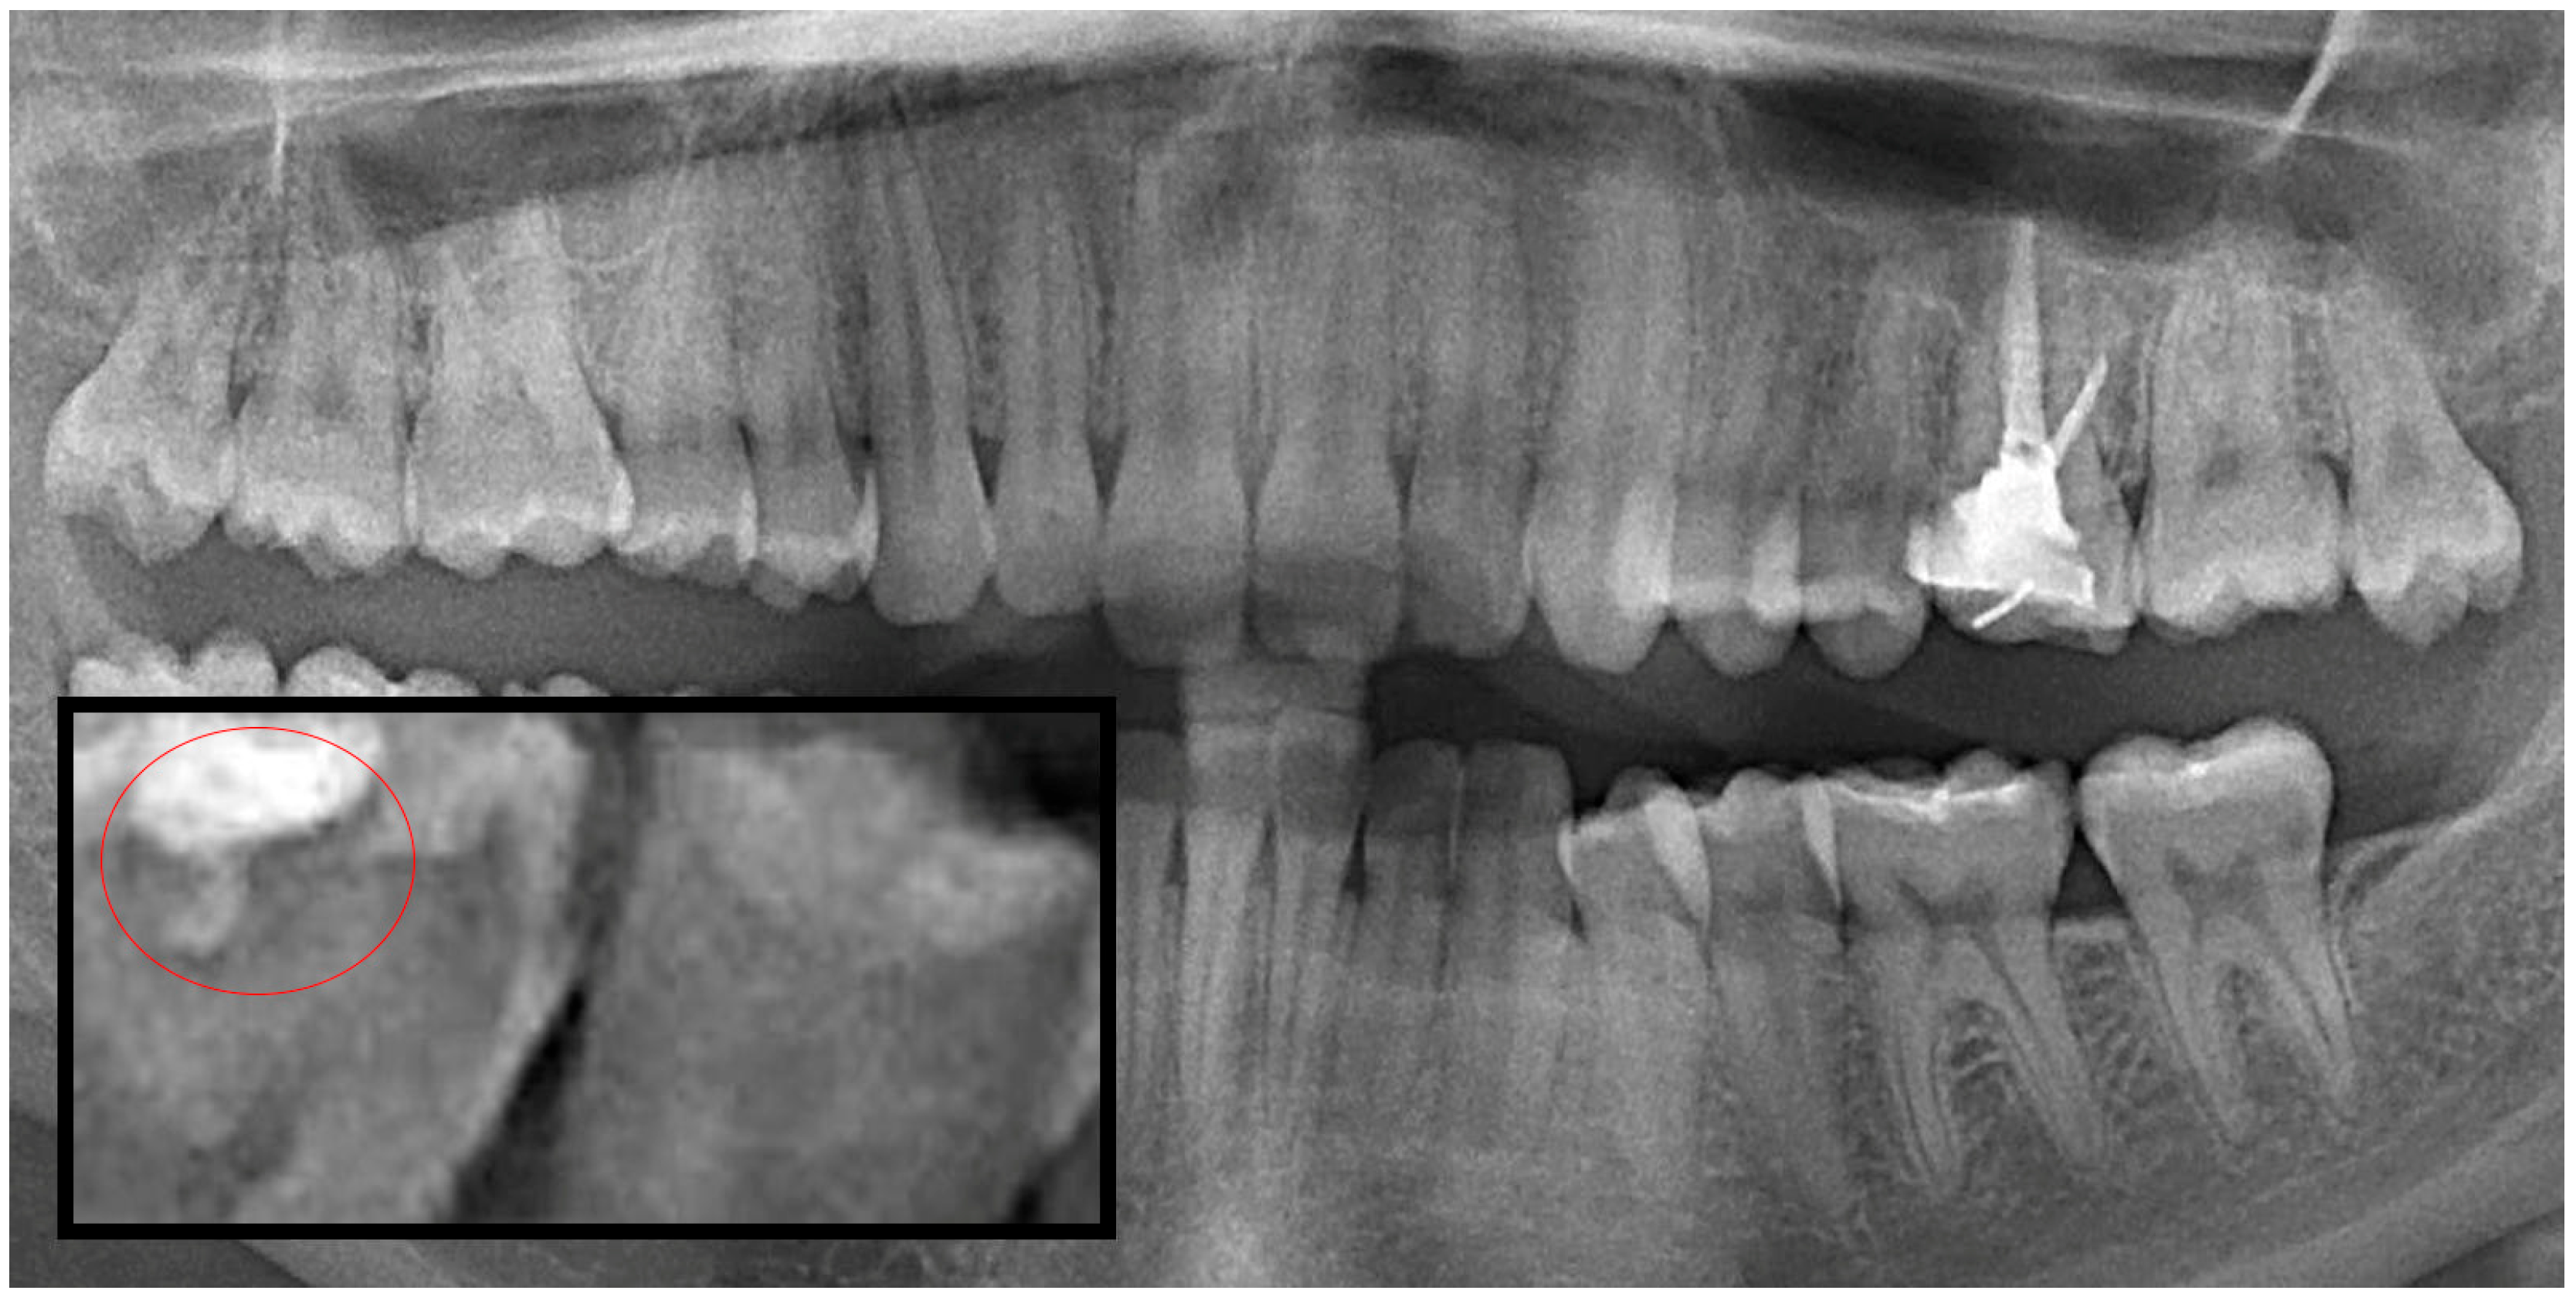

2.1. Evaluation and Categorization of Panoramic Radiographs

2.2. Image Processing and Segmentation